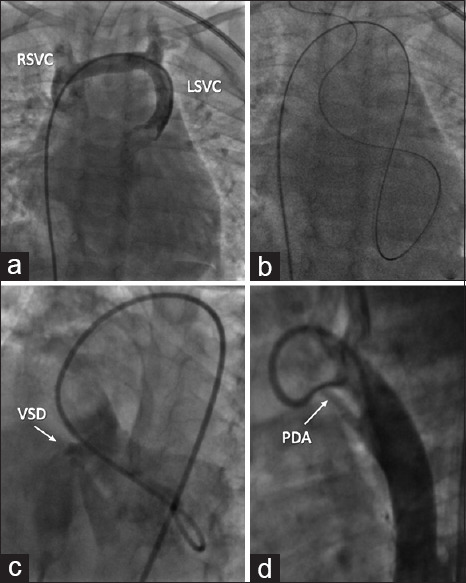

Coronary sinus (CS) defects are rare congenital cardiac anomalies that occur in isolation or with other congenital heart diseases. Persistent left superior vena cava (LSVC) is a relatively common entity that usually drains into the CS, is of no hemodynamic consequence, and is easily diagnosed on echocardiography by a dilated CS and an antegrade flow toward the heart. However, a combination of LSVC and CS defect may reverse its flow direction and CS dilation may be absent. In the absence of echocardiographic clues, the reversed flow can be easily misdiagnosed for other structures such as the more common vertical vein of anomalous pulmonary venous connection or the rarer levoatrial cardinal vein. Here, we report a 2-year-old boy with ventricular septal defect, patent ductus arteriosus, absent CS, and a persistent LSVC with retrograde flow producing a hemodynamically significant pretricuspid left-to-right shunt along with its diagnostic challenges. He underwent successful surgical closure of these defects and had been asymptomatic on follow-up.